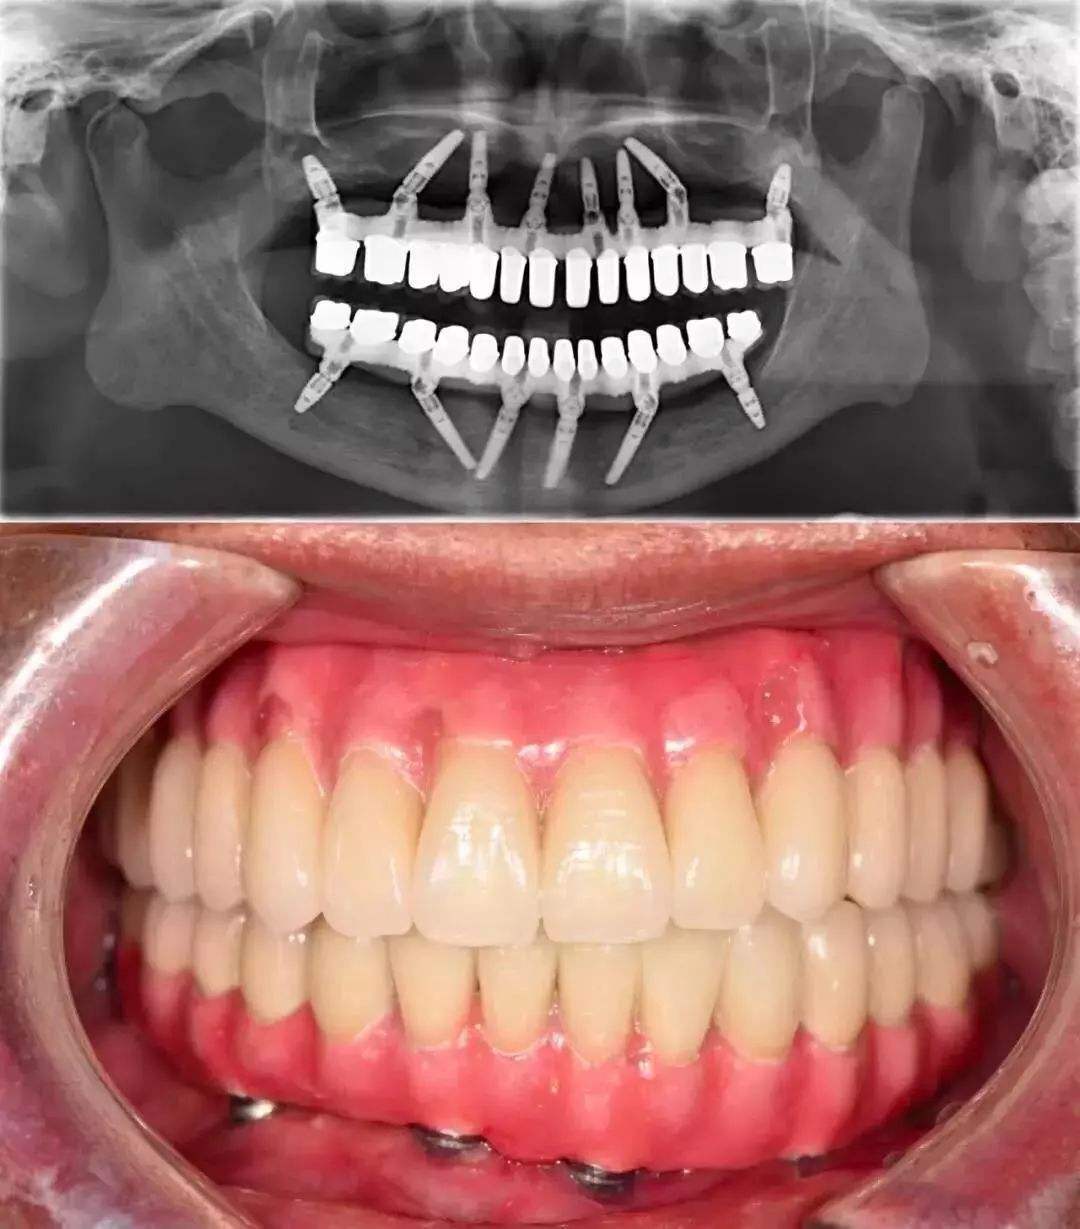

牙齿症状:牙齿几乎全口脱落,佩戴假牙过敏。

治疗方法:治疗口腔疾病,植入种植牙。

接下来医生告诉冯先生,种植牙手术不论是对患者还是操作医生都有很高要求。冯先生在做种植牙前,先要治疗口腔疾病。冯先生连连点头,表示完全配合。随后,口腔检查、制作种植牙手术导板、备制种植窝、备制螺纹,山西盛大齿科医院专家都认真征求了冯先生意见。直到植入种植体、缝合创口、带上牙冠。

冯先生说尽管整个种植过程时间不短,但是现在看着自己一口整齐的牙齿,再次体会到食物的鲜美,一切都是值得的。